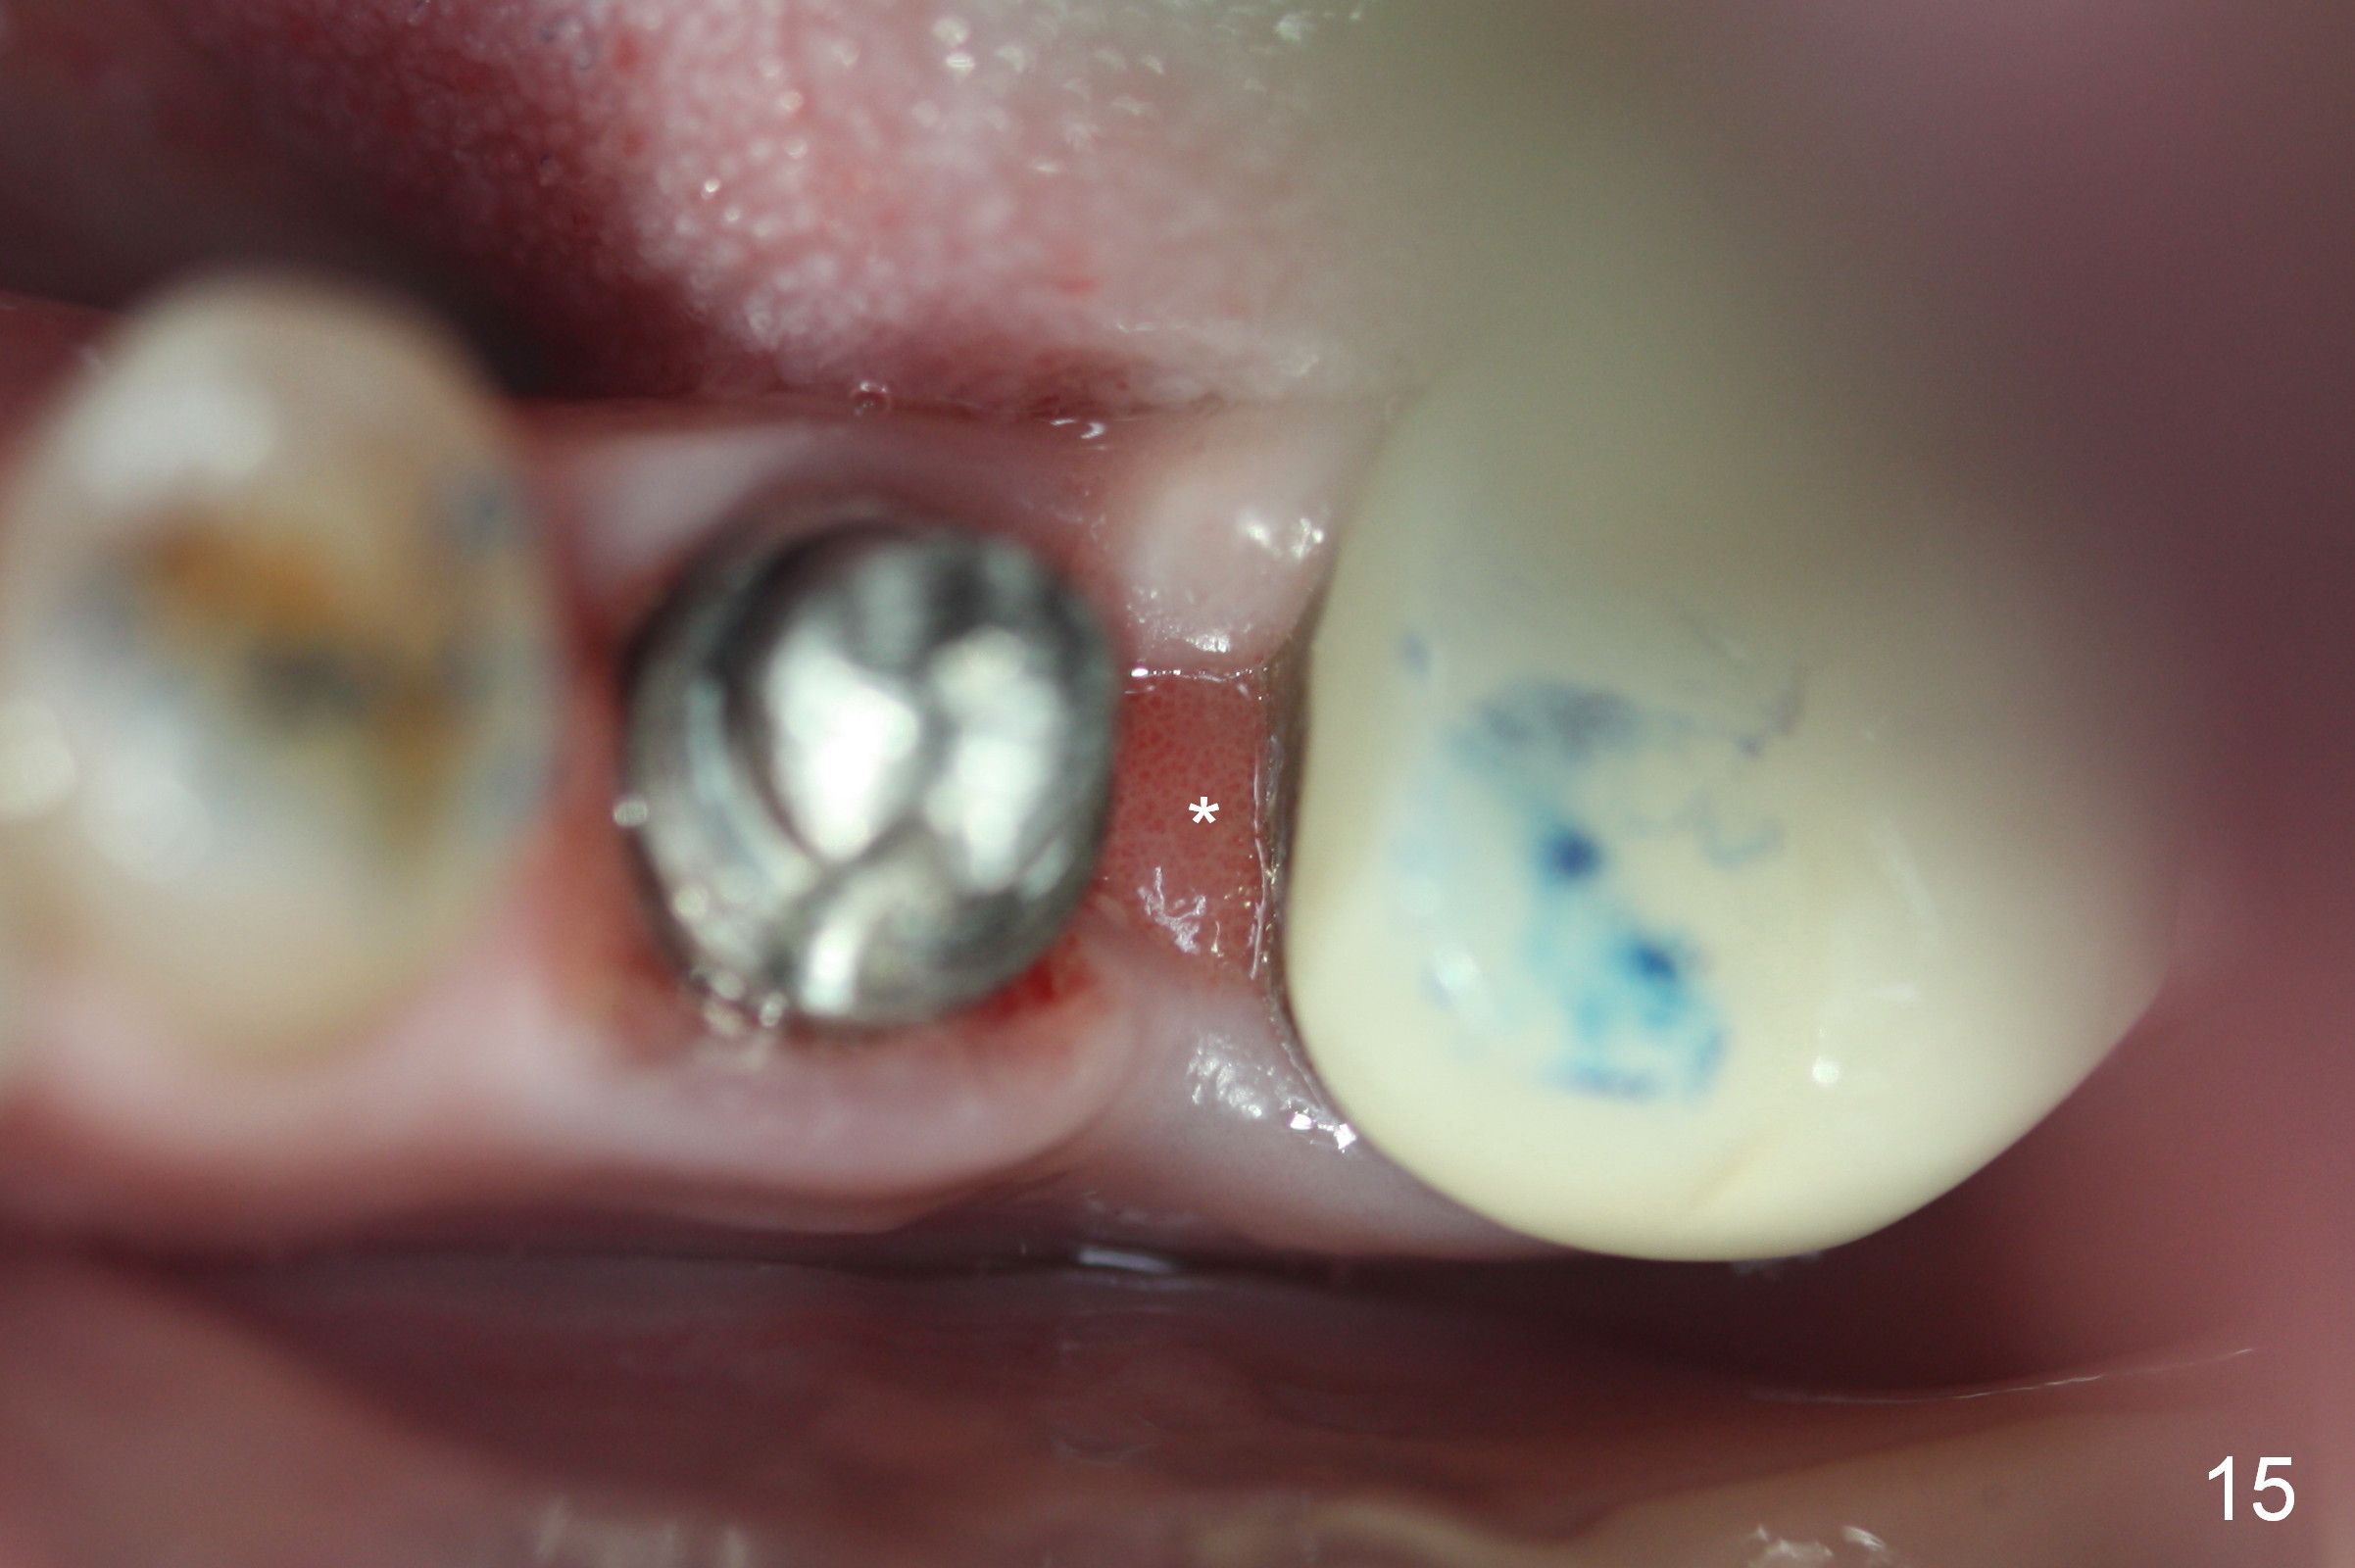

PA taken 3 months postop shows that the distal bone graft (Fig.14 *) appears to consolidate/sink down (arrow) to cover the implant threads. The distal gingiva remains to be fresh granulation tissue less than 4 months postop, immediately before crown cementation (Fig.15 *). The significance of the latter remains to be known. In fact, there is no problem in the distal embrasure. Two and a half months after cementation, the patient returns requesting remaking the crown, since food is easily impacted mesially with floss trauma, as shown by arrowhead in Fig.16.